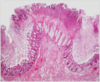

What is this?

cryptosporidosis

C. parvum infection